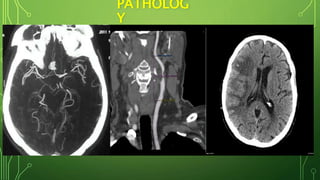

PATHOLOG

Y